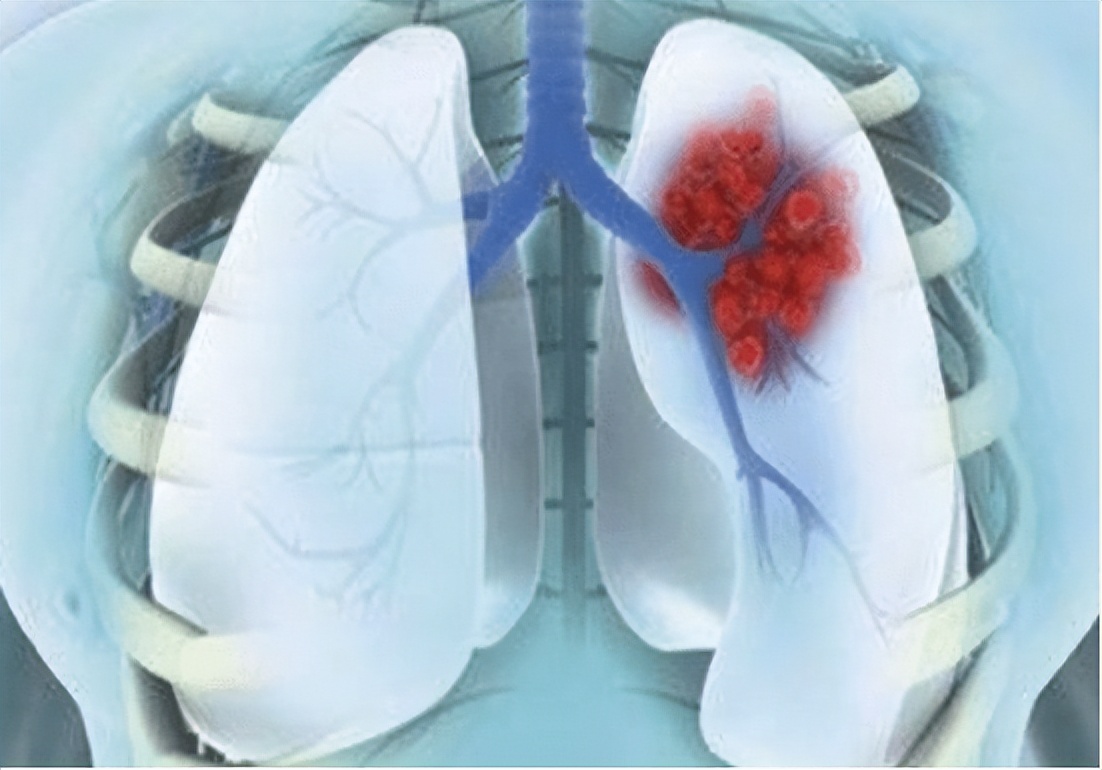

和肩周炎症患者不一样,肺部出现肿瘤的人的痛感是放电般的感觉,尤其在剧烈的时候身体会不由自主地抖动,肩背部感觉麻麻的,它没有明显的疼痛点,患者对于这种痛感描述为片状。 而且肺癌患者不会忌讳凉水、冷风等寒性物质,这就是因为肺癌的原因是病毒或者肿瘤的扩散导致,并不是骨科和韧带的原因。

王大爷就是有这种体会,往常如果劳作辛苦、肩膀疼痛,贴上一副膏药就会缓解不少。但是近日来的肩背疼痛和以前大不相同,不仅贴膏药也无济于事, 反而还要吃专门的止痛药才能缓解一二。他能明显地感觉到,即使止痛药缓解了一时半会儿的疼痛,过段时间还是会复发并且会愈演愈烈。